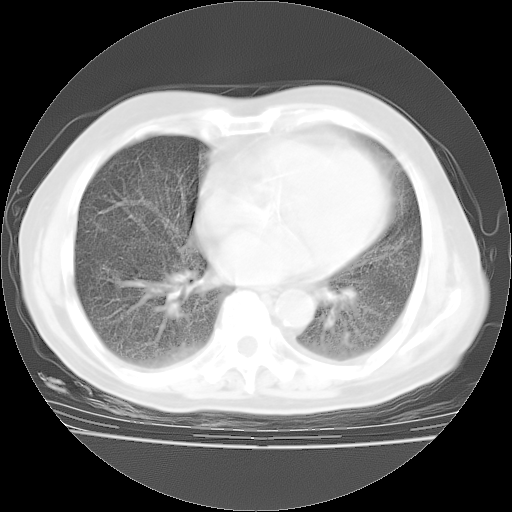

肺部CT平扫未见异常。